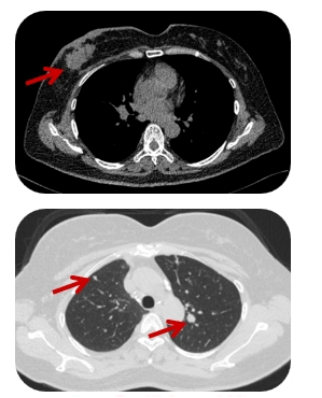

疾病进展 (2024.07.22):复查评估提示右乳病灶增大,侵犯皮肤,肺部出现新发病灶。

疾病进展 (2025.01.22): 评估显示右乳病灶再次增大并出现破溃。